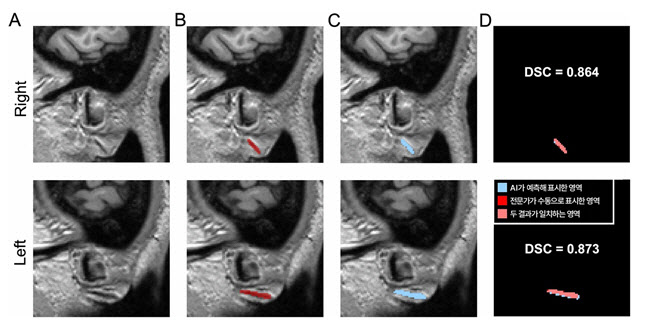

분당서울대병원에서 수집한 400건의 뇌 MRI를 바탕으로 전문가가 수동으로 구분하고 표시한 프랭크 징후를 AI에 학습시켰다. 이후 학습에 사용하지 않은 별도의 분당서울대병원 데이터셋(총 600건)으로 1차 검증, 충남대병원·강원대병원·세브란스병원 다기관 데이터셋(총 460건)으로 2차 검증을 진행했다.

검증 과정에서는 전문가가 수동 표시한 프랭크 징후 영역과 AI가 자동으로 분할한 영역을 비교해 AI의 정확도를 평가했다. 여기서 ‘분할(segmentation)’이란 색칠 공부할 때 특정 부분만 색을 칠하듯이, AI가 귓불 주름을 찾아 표시하는 작업을 의미한다.

그 결과, 전문가가 수동으로 표시한 영역과 AI가 자동으로 분할한 영역의 일치 정도를 측정하는 DSC(Dice 유사도 계수, 1에 가까울수록 유사) 값이 두 차례의 검증에서 0.734, 0.714로 나타났다. 이는 AI가 찾아낸 영역이 전문가의 판단과 70% 이상 부합한다는 뜻으로, 의료영상 분야에서 높은 수준으로 인정받는다.

3차원 원본 이미지(A)를 토대로 전문가가 수동으로 직접 표시한 주름(B)과 AI가 예측해 자동으로 표시한 영역(C).

DSC 값은 두 영역의 겹침 정도를 수치화한 것으로, AI가 전문가와 거의 일치하게(약 87%) 주름을 찾아냈다는 의미를 가진다.

DSC 값은 두 영역의 겹침 정도를 수치화한 것으로, AI가 전문가와 거의 일치하게(약 87%) 주름을 찾아냈다는 의미를 가진다.